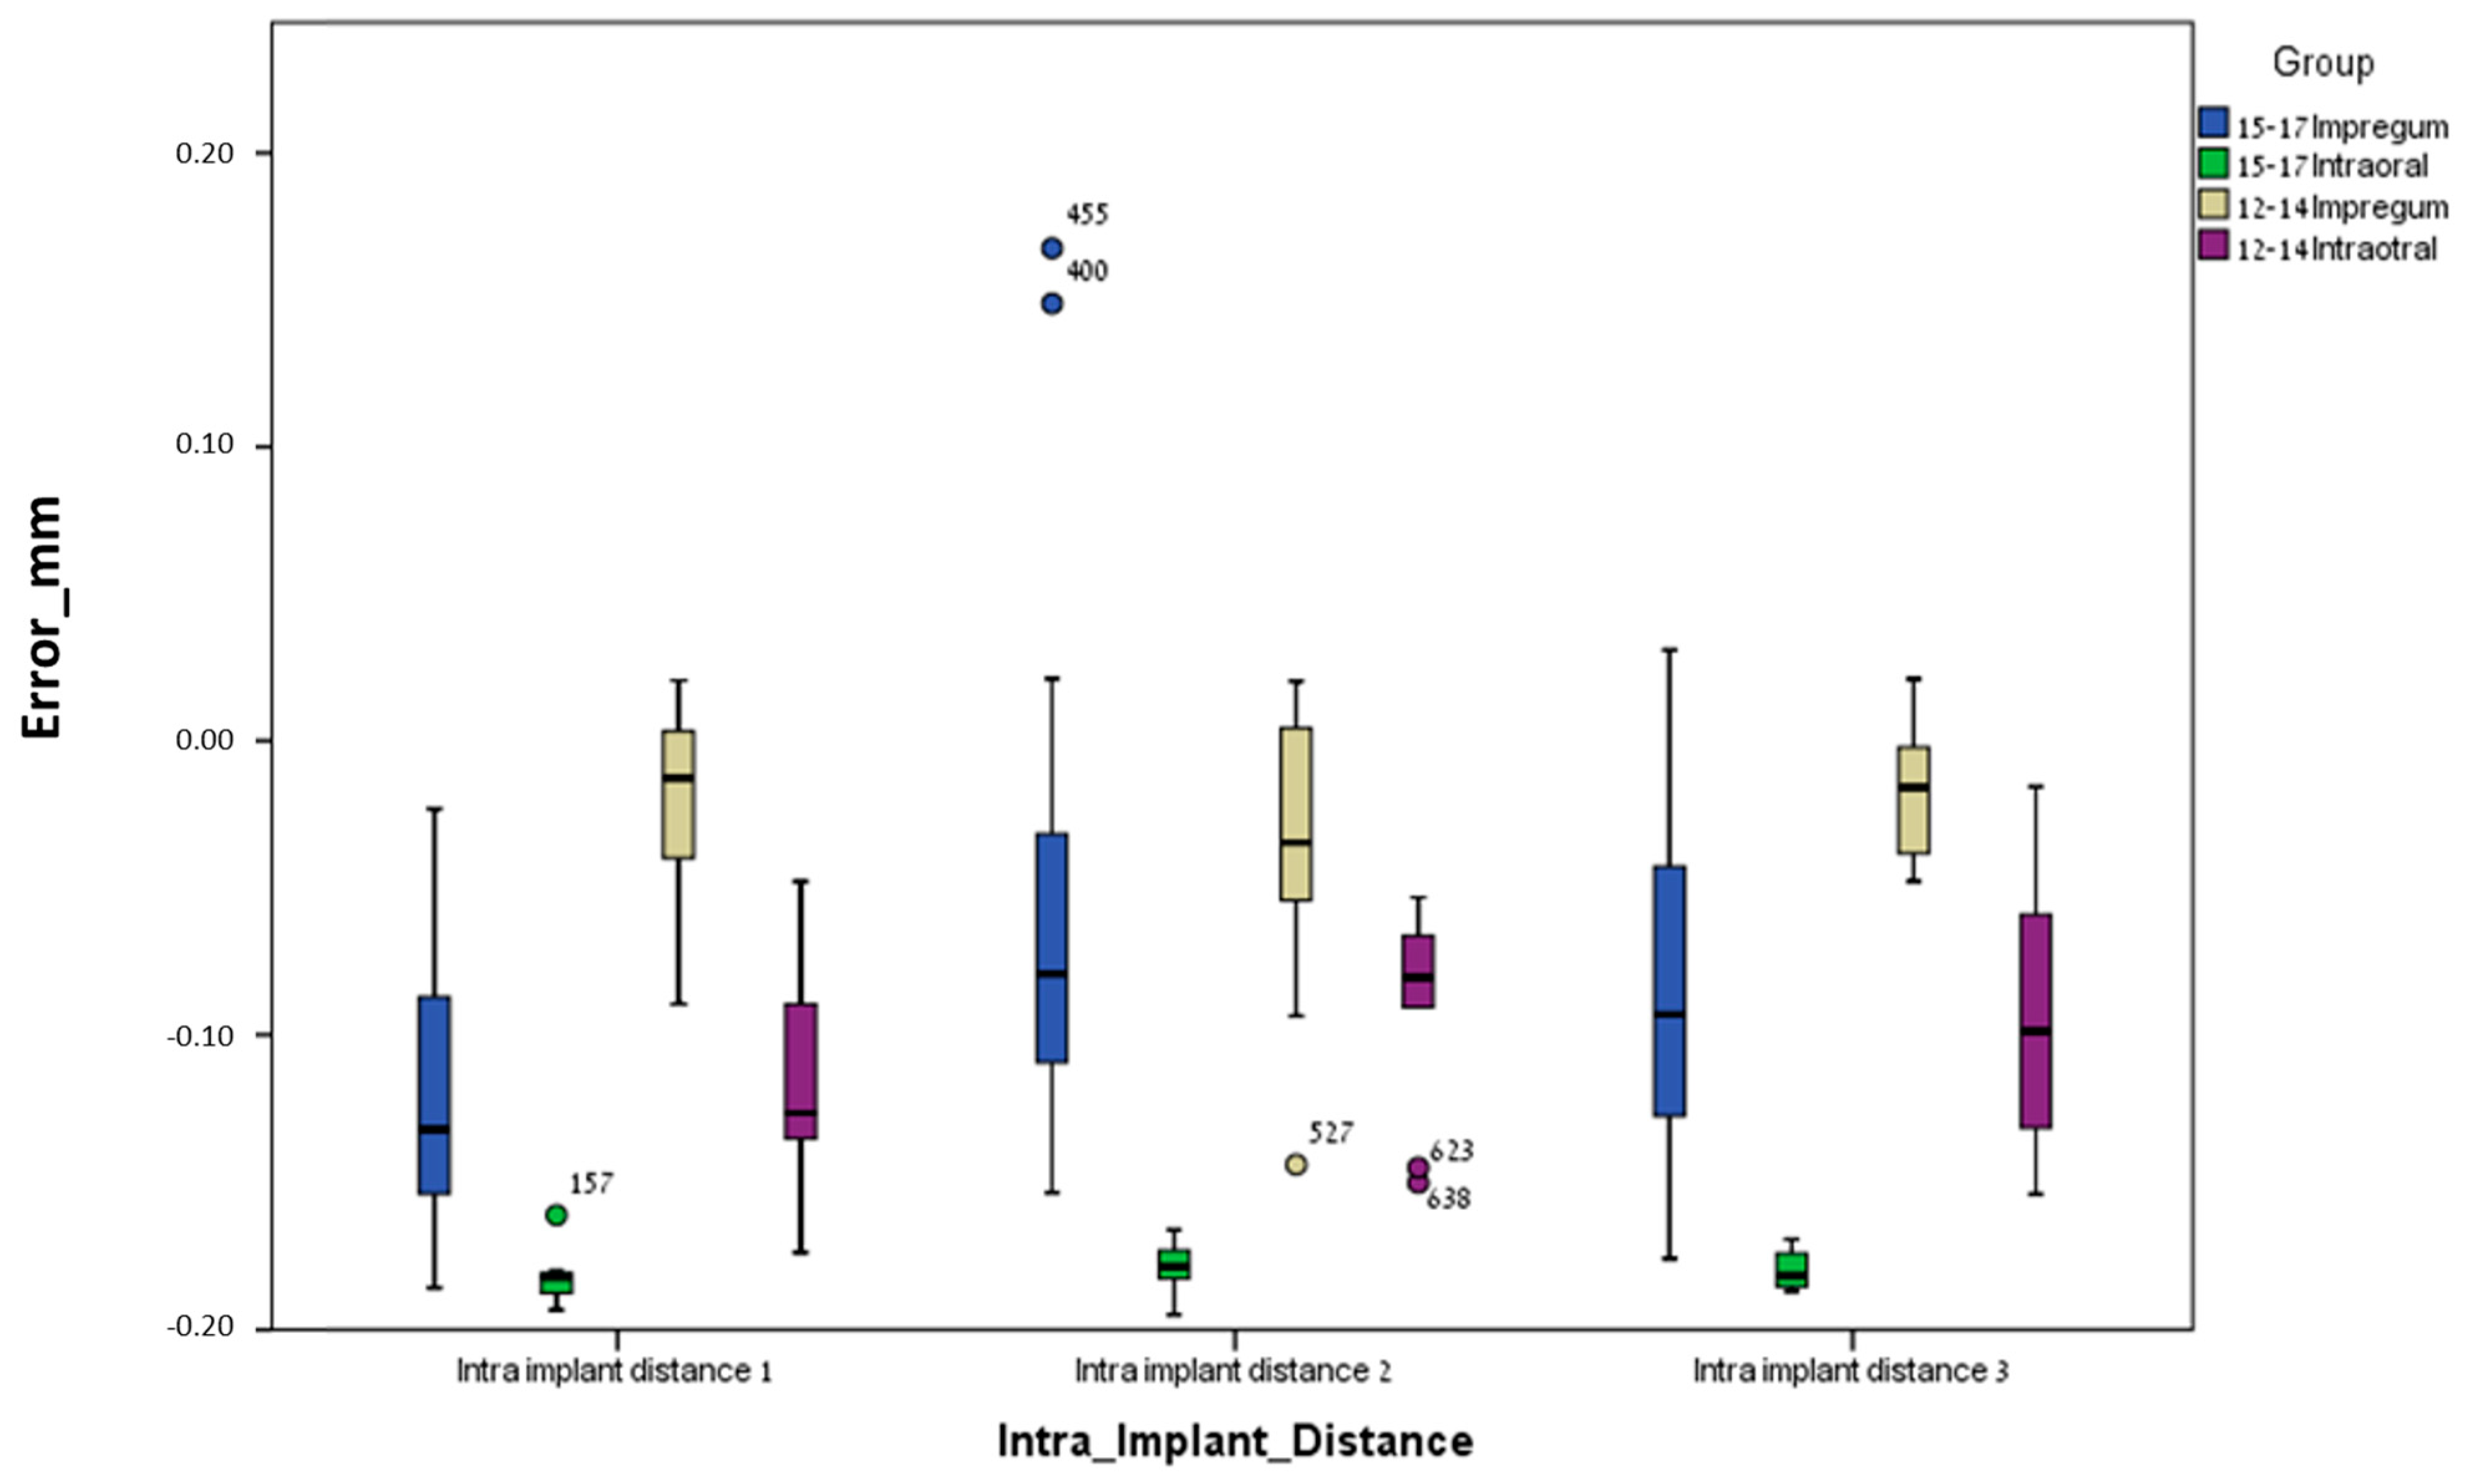

3. Results

3.1. Between Groups

3.2. Within Groups